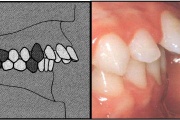

Normaalse jäävhammaskonna pilt küljelt ja eest vaadatuna.